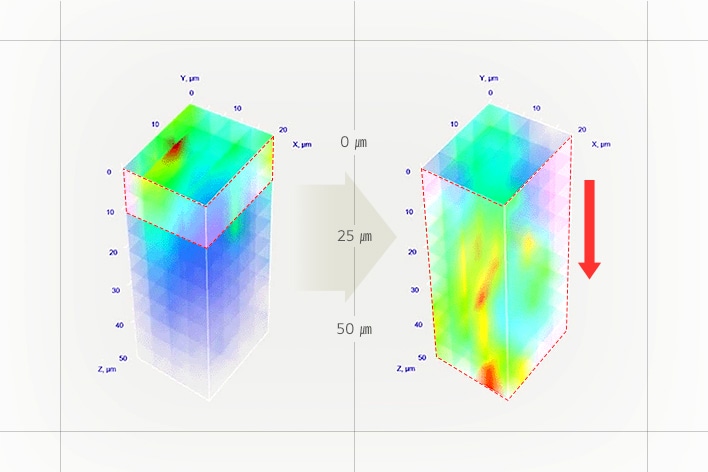

3) Excellent absorbency

-Skin Booster Boosting Mode in level 6 for 3 minutes

-Human application test results: Use of TOXNFILL Hyaluronic Boosting Ampoule / Comparison between two control groups, Skin Booster + Cosmetics vs. Hand + Cosmetics /

After absorption of the ampoule and a 30-minute wait, the degree of absorption, absorption amount, absorption depth, and absorption speed of the ampoule were measured using Raman microscopy, and the improvement rate compared to the Hand + Cosmetics control group was expressed in a %.

-February 5 - February 16, 2024 / 20 adult women (including 10 with sensitive skin) / P&K Skin Clinical Research Center

-Test results have been excerpted from the test performance report for consumer understanding.

-There may be personal differences depending on individual skin characteristics or skincare product combinations.